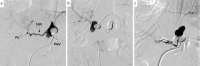

A 42-year-old woman visited our hospital due to syncope. Contrast-enhanced CT revealed portosystemic shunt, portal vein hypoplasia, and multiple liver nodules. The histological examination of a liver biopsy specimen exhibited portal vein hypoplasia and revealed that the liver tumor was positive for glutamine synthetase. The patient was therefore diagnosed with congenital extrahepatic portosystemic shunt type II, and with focal nodular hyperplasia (FNH)-like nodules. She had the complication of severe portopulmonary hypertension and underwent complete shunt closure by balloon-occluded retrograde transvenous obliteration (B-RTO). The intrahepatic portal vein was well developed at 1 year after B-RTO, and multiple liver nodules completely regressed. Her pulmonary hypertension also improved.